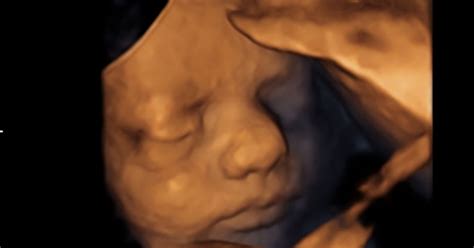

- Spontani splav (izostali splav): V tem primeru je nosečnost izgubljena, vendar se ženska tega morda ne zaveda. Ultrazvok potrdi, da plod nima srčnega utripa, čeprav morda ni izrazitih simptomov spontanega splava.

- Popoln splav: Nosečnost je izgubljena in maternica je popolnoma prazna. Ženska je doživela krvavitev in izločila vse fetalno tkivo. Zdravnik lahko s pomočjo ultrazvoka potrdi, da je prišlo do popolnega spontanega splava.